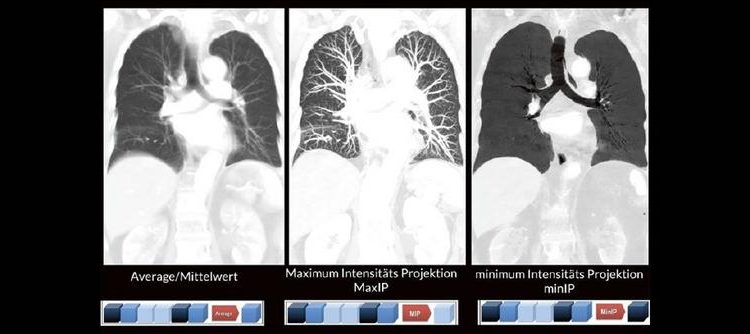

Alex Riemer Moderne CT-Scanner unterstützen die Anwenderinnen und Anwender bei der Durchführung der meisten CT-Untersuchungen. Hierzu zählt auch das automatische Erstellen von streng coronalen und sagittalen Multiplanaren Reformatierungen (MPR´s). Es gibt jedoch CT-Untersuchungen, bei denen die MPR´s individuell an die Anatomie angepasst werden müssen. Doch gerade bei diesen Bildnachverarbeitungen gibt es oft Unsicherheiten darüber, worauf […]